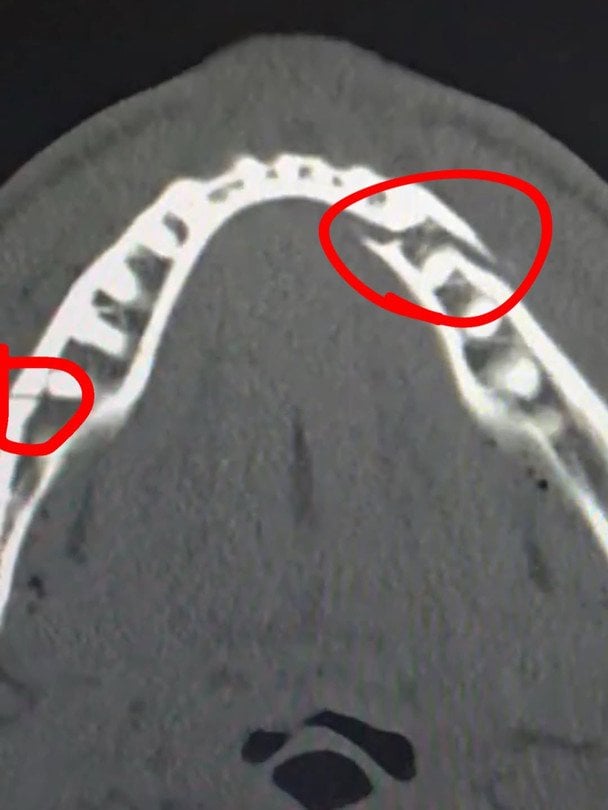

Пол вирушив до лікарні, де зробив рентгенівський знімок, який показав, що у нього зламана щелепа у двох місцях.

"Перелом щелепи в двох місцях. Дайте мені Канело через 10 днів", – написав Пол.

Зламана щелепа Джейка Пола / instagram.com/jakepaul